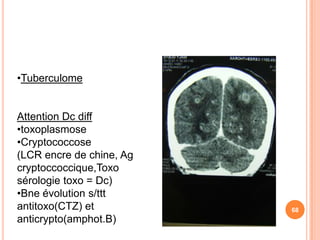

•Tuberculome

Attention Dc diff

•toxoplasmose

•Cryptococcose

(LCR encre de chine, Ag

cryptoccoccique,Toxo

sérologie toxo = Dc)

•Bne évolution s/ttt

antitoxo(CTZ) et          68

anticrypto(amphot.B)